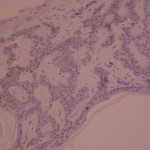

Ki-67 staining of an acantho-hyperkeratotic type of SK. On the last picture, most of the basal staining comes from the accumulation of pigment as the clinical image suggests.

Ki-67 staining of an acantho-hyperkeratotic type of SK. On the last picture, most of the basal staining comes from the accumulation of pigment as the clinical image suggests.

Ki-67 staining of an acantho-hyperkeratotic type of SK. On the last histological picture, most of the basal staining comes from the accumulation of pigment as the clinical image suggests.